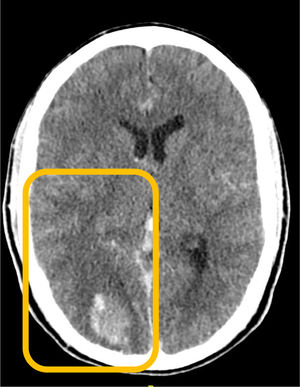

This is the case of a man with soft tissue septic shock due to Streptococcus pyogenes after trauma. Hematogenous spread with necrotizing fasciitis in the extremities (surgical resection) and meningitis with brain abscess (craniectomy and evacuation). Computed tomography (CT) with contrast: edema in the subcutaneous tissue of the left arm and muscle bellies, and a collection on the medial side of the right leg (Fig. 1, blue arrow). Right parietooccipital lobar cranial hematoma, vasogenic edema, and traumatic subarachnoid hemorrhage in the cisterns, with an increased mass effect (blurring of sulci and compression of the right lateral ventricle) (Fig. 2, orange box). Cranial MRI after clinical deterioration (Fig. 3): right occipitotemporal collection of 3.5 cm × 9 cm, irregular hypercaptating margins, and restriction (red stars) suggestive of brain abscess, with intraventricular pus, subfalcine herniation, right uncal herniation (red arrows), and subdural hematoma at the craniectomy site (red triangle).